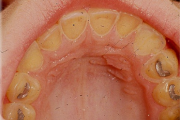

Lutipudelikaariese kahjustused

Lutipudelikaaries